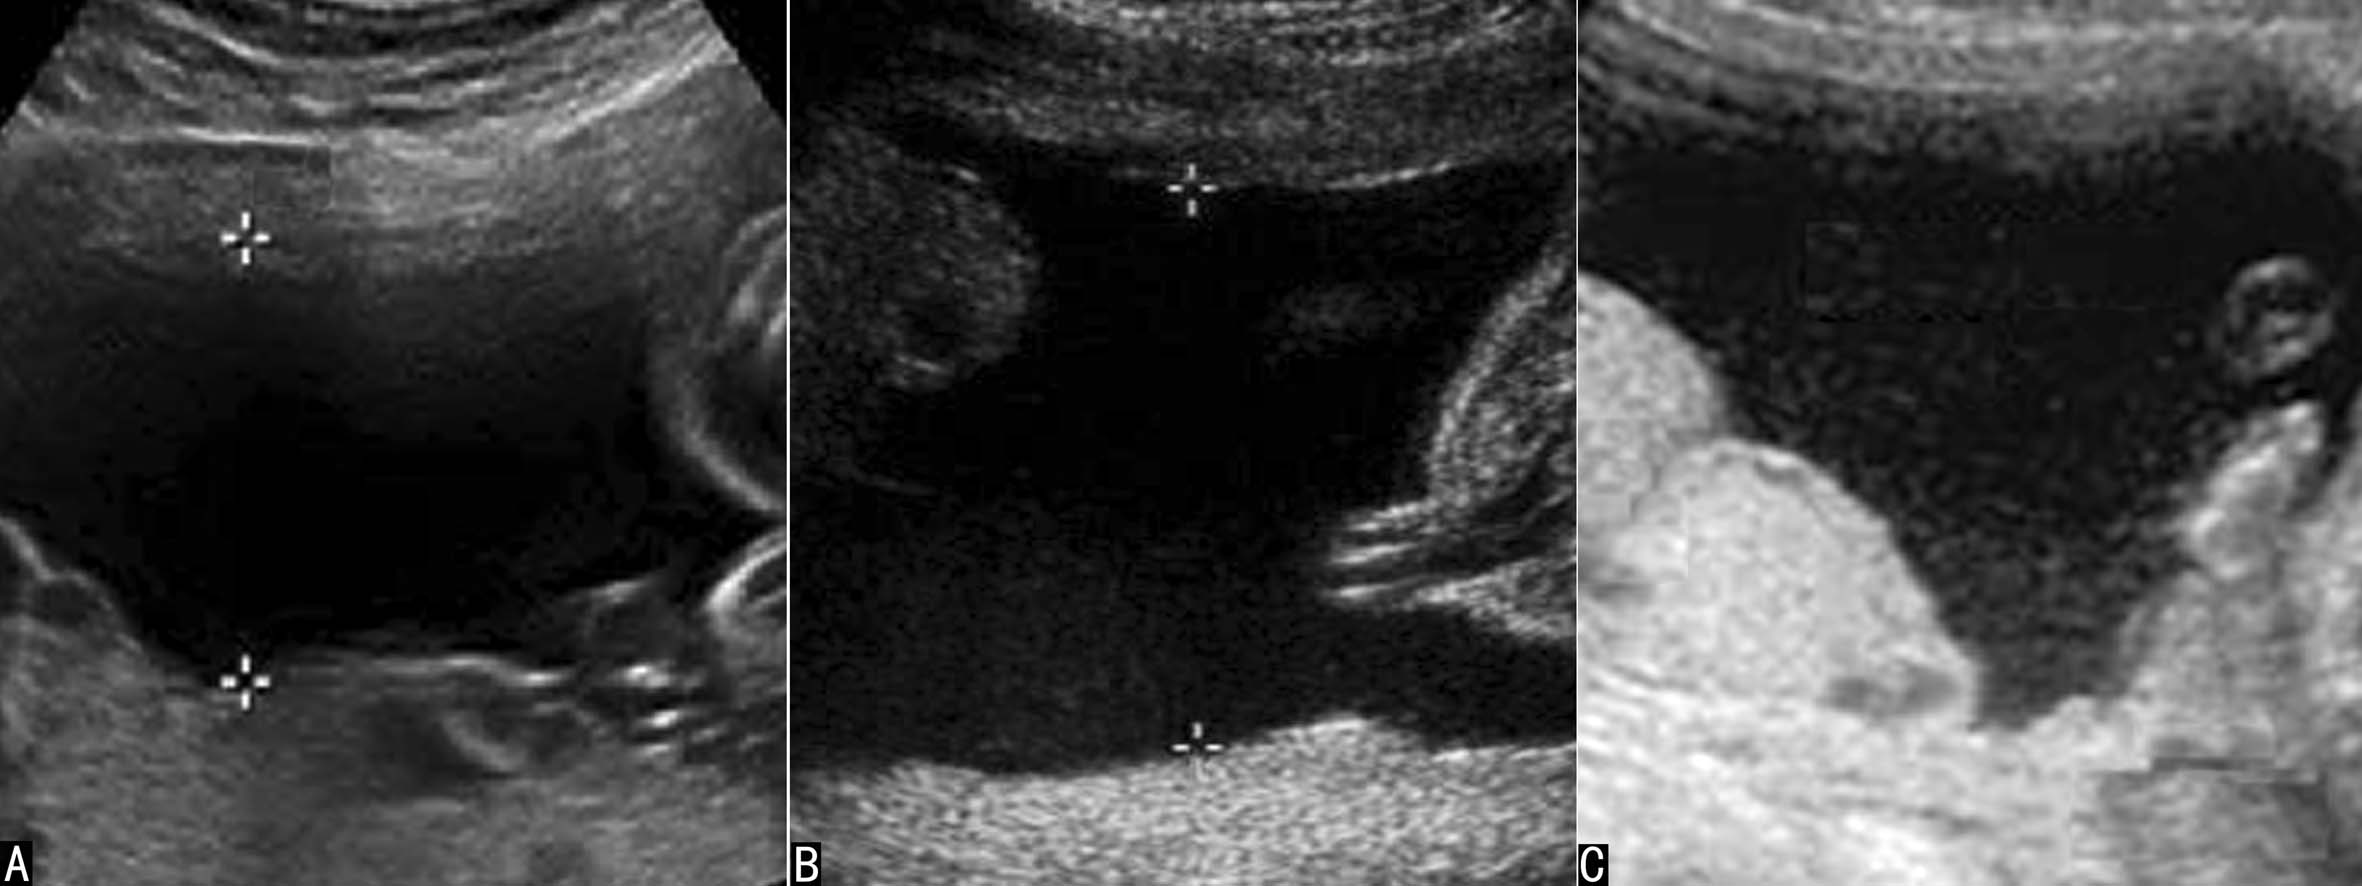

图2中晚期妊娠羊水显示

晚期妊娠过程中羊水声像图的变化较快,主要表现在羊水回声性质的改变和羊水量的减少,应当注意适时检查并作出相应的评价。晚期妊娠时羊水内部的点状回声逐渐增多,在胎儿活动时可以发现少许漂起的点状回声,停止活动后回声点可以缓慢下落;越临近分娩,羊水内部的点状回声越多(见图2C)。这些漂浮的回声可能与胎儿皮肤脱离的皮脂有关。过期妊娠或胎儿宫内窘迫时常可在短期内发现羊水内点状回声明显增多,严重时羊水内可见弥漫分布的均匀、低水平的点状回声,脐带血管在其内显示为纯净的无回声区,同时伴有羊水量的减少。

2.羊水池内径测量法 将探头垂直于子宫壁,测量羊膜腔内侧壁至胎体最大的距离,此即羊水池的最大内径。以获得的数值衡量羊水量多少。正常时羊水池内径4~6cm。小于2cm为羊水过少,大于8cm为羊水过多。也有研究者将超声探头垂直于水平面,测量羊水池最大的垂直深度。这种方法也被称为羊水池最大垂直深度测量法(图3)。

图3羊水池最大内径测量